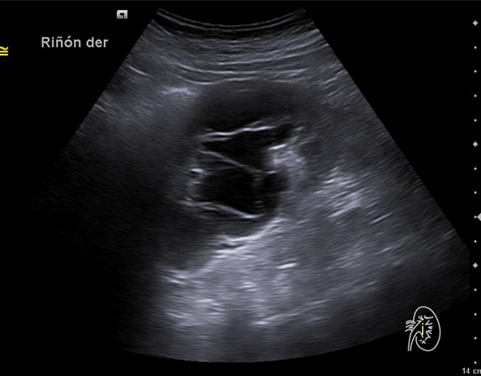

Riñón derecho 9,9 cm con morfología y ecogenicidad conservada. Presenta hidronefrosis grado III. No se identifica causa obstructiva.

Se remite a la paciente a Urgencias donde fue dada de alta con diagnóstico de CRU y tratamiento con Fosfomicina. Consultó al día siguiente, persistiendo el dolor y febrícula, remitiéndose de nuevo a Urgencias. Solicitan estudio de imagen con ecografía y ante los hallazgos se amplió el estudio a TC simple de abdomen: Hidronefrosis grado III con líquido perirrenal sugestivo de rotura de fórnix. Nefrolitiasis puntiformes en ambos cálices inferiores. Sin clara causa obstructiva objetivable. Se contactó con Urología de guardia quien propuso tratamiento ambulatorio con seguimiento posterior y colocación de nefrostomía programas y pielografía para estudio de probable estenosis de unión pieloureteral. Actualmente la paciente permanece en seguimiento por urología.